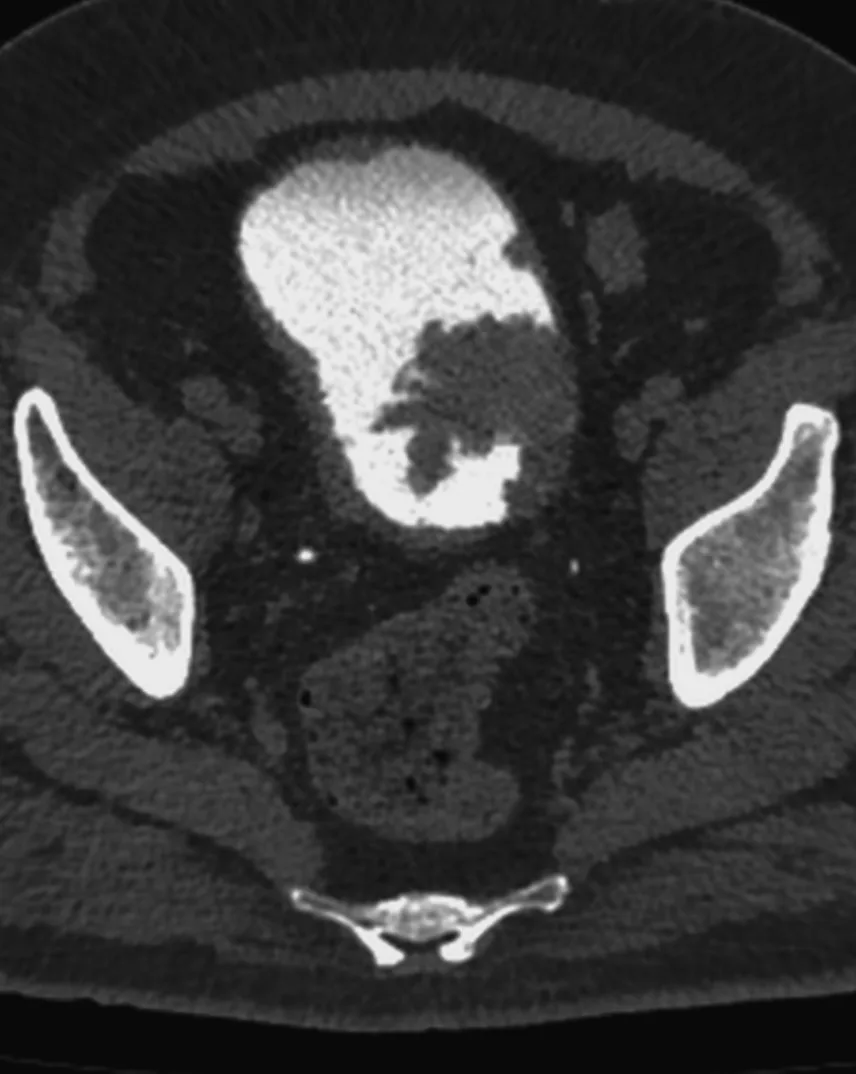

Сделали мочевой пузырь с контрастом, оказалось три образования в стенке, категория по ви-рац – четвёрка.

То, что по КТ выглядело, как огромное образование, по большей части оказалось кровяным сгустком. Оценить стенку на мрт с контрастом оказалось возможным только благодаря вычитанию, рекомендуем это всем, кто занимается оценкой стадий рака мочевого пузыря на МРТ. Помогает, когда внутри сгустки крови, яркие на нативной T1W.

Вот и думай теперь, что с этим делать. Пузырь удалять?